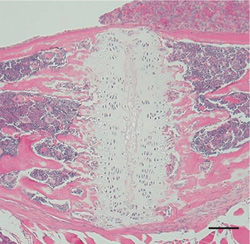

図3: 蝶後頭軟骨結合部 マウス頭蓋矢状断像

左:BALB/c系マウス、 右:BALB/c-bm/bm, 軟骨の形成に明らかな違いが認められる。